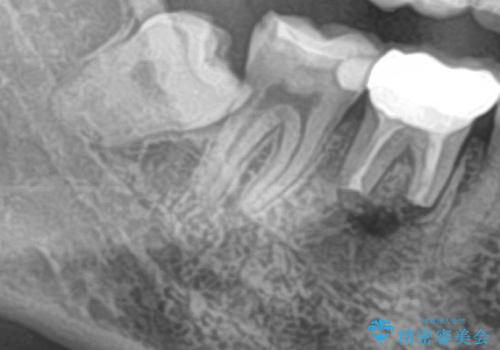

- 右下の親知らずを抜きたいとのことで来院された患者様です。

CTで神経の位置などを確認し、抜歯術を行いました。